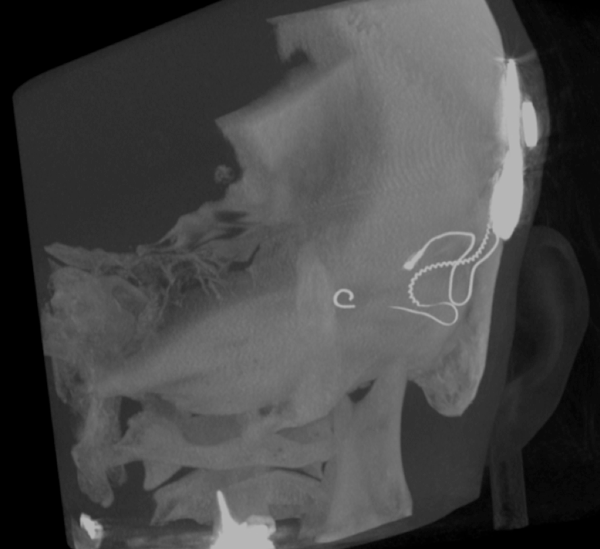

Both patients were imaged immediately with CBCT using SCANORA® 3Dx (Soredex, Tuusula, Finland). The field of view (FOV) was 140 x 165 mm and voxel size 0.2 mm. Imaging parameters were 90 kV, 8 mA, 4.00s. Standard 1 mm axial, coronal and sagittal reformations were made, as well as MIP and 3D reconstructions using OnDemand3D™ software (Cybermed, Seoul, South Korea).

CBCT proved to be optimal for imaging of these implants because of the superior bony delineation and nearly artefact free images. All four parts, i.e. the receiver stimulation part, extracochlear electrode implanted on the surface of the temporal bone, the extracochlear electrode plate and the intracochlear electrode array could be well imaged with CBCT.

On CBCT all four of the important parts of the implant were very well seen both on the axial slices and three dimensional surface reconstruction images. The implant is placed on magnetic plates, and the extracochlear part was seen in an abnormal separated position. The intracochlear electrode array showed no signs of separation in either of the cases. The intracochlear electrodes were well seen in both of the cases.

Figure 2: 3D MIP image of patient 1.